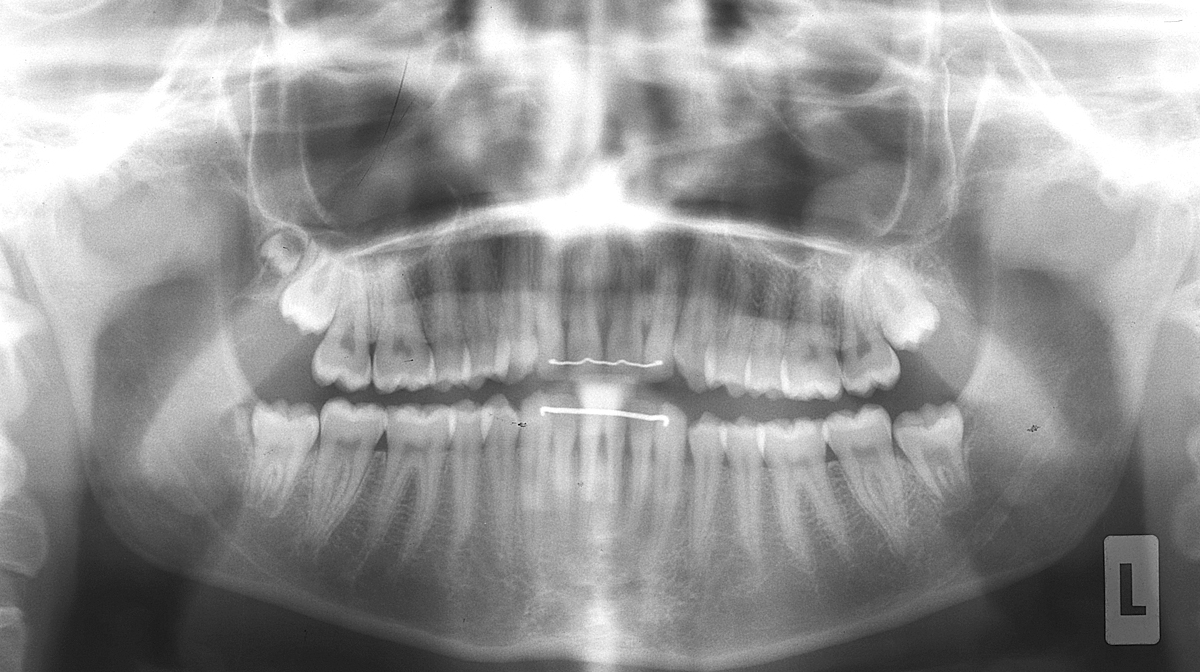

Anbei ein Fall eines 15-jährigen Mädchens, das auf der rechten Seite sogenannte «9er» hat (überzählige Zähne ganz «hinten», anschliessend an die Weisheitszähne).

Sie sind unten auf den Röntgenbildern dargestellt und markiert.

Panorama-Röntgenbild (Orthopantomogramm, OPT)